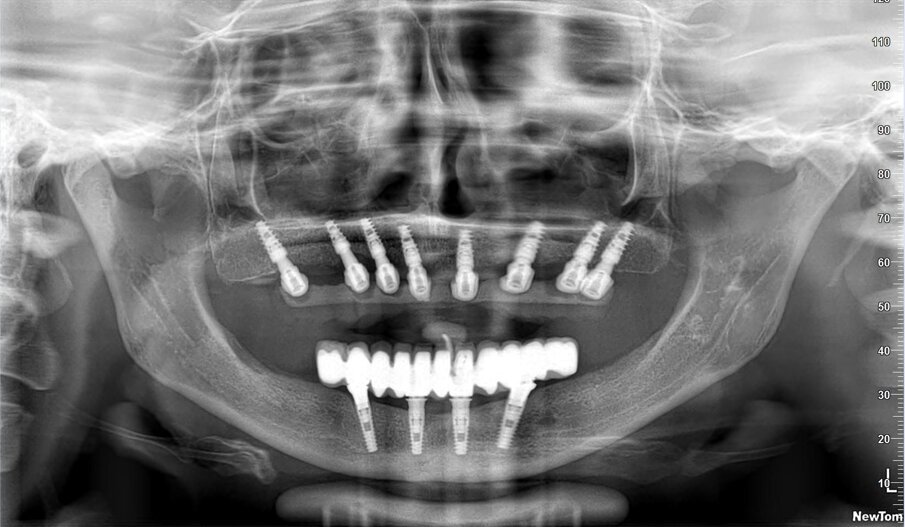

La resina alla stato ancora tenero va indurita con la lampada polimerizzante per alcuni minuti; una volta controllata la masticazione anche senza la chiave articolare e fatti gli opportuni minimi ritocchi, la protesi va rimossa e rifinita a dovere, poi riaccoppiata. Una OPT di conferma serve per verificare il corretto alloggiamento delle cappette sui monconi e la passività del manufatto.

Le tabelle 1-8 mostrano, su un totale di 313 impianti eseguiti tra arcata superiore (208) e inferiore (105), che la tecnica non ha alcuna complicanza biologica a 3 anni di esecuzione, non sono stati evidenziati fallimenti implantari in arcata inferiore (18 pazienti), solamente 5 in arcate superiori tutti nella zona molare (29 pazienti). In 1 paziente è stata registrata una frattura della protesi dovuta a eccessiva distanza tra gli impianti (zona laterale superiore e tuberosità) con antagonista naturale senza presenza di molari; 3 fratture dei denti in pazienti con bruxismo e serramento; circa la metà dei casi (140 impianti) è stata eseguita in condizione post-estrattiva e alcuni casi sono stati caricati con metodiche avanzate di rialzo di seno mascellare (11 pazienti) e 1 con Split Crest. Tutti gli impianti sono stati caricati immediatamente, anche quelli nei settori posteriori superiori o nella tuberosità.